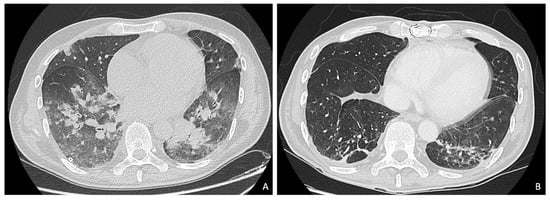

A 50-year-old man with no co-morbidities presented with pneumonia after unsuccessful empirical treatment at home with levofloxacin 750 mg/day. The patient was first admitted in the pneumology department, but the main infectious disease analyses (H1N1, HIV, quantiferon, and legionella-pneumococcal-mycoplasma antigens), as well as the first nasopharingeal swab test for SARS-CoV-2 results were negative. Due to the sudden development of heart failure, the patient was transferred to the cardiac-ICU, where a trans-oesophageal echocardiography (TOE) showed a tricuspid aortic valve affected by endocarditis, with multiple motile vegetations above the cusps (the major one of 2 × 0.5 cm2 on the non-coronary cusp), resulting in severe aortic regurgitation (AR) (Figure 1 and Supplemental Video S1). A concomitant severe mitral regurgitation (MR) due to prolapse/flail of the myxomatous antero-lateral scallop of the posterior leaflet (P1) and a mildly reduced left ventricle ejection fraction (LVEF) (50%) were also observed. Later, a second SARS-CoV-2 nasopharyngeal swab test result was positive and a total-body computed tomograpy (CT) scan confirmed the presence of a COVID-19 pneumonia, with bilateral apical and midfield ground glass pattern (Figure 2A and Supplementary Video S2), with hepatic and also splenic endocarditis embolizations. The patient was initially treated with i.v. 2 g vancomycin and 360 mg gentamicin daily, followed by 700 mg of daptomycin and 3 g meropenem per day, although the first six sets of blood culture results were negative. The presence of abundant pleural effusion required percutaneous bilateral drainage, while high-dose inotropic support and non-invasive ventilation (NIV) with continuous positive airway pressure (CPAP, 10 cmH2O, FIO2 0.6) were started due to progressive hemodynamic and respiratory deterioration, obtaining adequate gas exchange, thus, avoiding the need for orotracheal intubation (OTI) and prone positioning [5,6]. Then, the patient was transferred from the spoke unit (Sant’Anna Hospital, Como) to the central hub (San Raffaele University Hospital, Milan), since urgent surgery was indicated, despite increased surgical risk (STS, 4.8%) [1,7]. Here, after exclusion of QT interval abnormalities, immunomodulation therapy against SARS-CoV-2 with hydroxychloroquine 200 mg twice a day was added [8]. Contemporarily, the patient underwent an aortic valve replacement with a 23 mm Perimount bioprosthesis (Edwards Lifesciences Inc., Irvine, CA, USA) and a concomitant mitral valve repair with an antero-lateral para-commissural edge-to-edge (A1-P1) technique and a 37 mm Simulus partial flexible posterior prosthetic ring (Medtronic Minneapolis, MN, USA). Extra-corporeal circulatory (crystalloid Custodiol cardioplegia) and aortic cross-clamp times were 96 and 83 min, respectively. The patient entered the hub hospital in a dedicated COVID-19 pathway, which consisted of a specific COVID-19 negative pressure OR, with a postoperative stay reserved in the COVID-ICU/ward. In addition, healthcare personnel directly involved were required to use specific protections (i.e., FFP2/3 mask) to prevent droplets/contact transmission.

Figure 2.

Pre- and post-operative thoracic computed tomography (CT) scan. CT imaging showing COVID-19 pneumonia (A) and its resolution (B) after three months.

During the ICU post-operative stay, the patient required circulatory high-dose inotropic (≥0.1 mcg/kg/min of epinephrine and norepinephrine) and mechanical support with IABP due to severe biventricular dysfunction. One cycle of levosimendan 0.4 mcg/kg/min was successfully performed over 96 hrs. After six days, the respiratory function progressively recovered, and the patient was extubated. Further application of CPAP guaranteed optimal oxygen saturations. Development of post-operative fever and evidence of Candida parapsilosis on the tip of the central venous catheter and blood cultures as well, required the introduction of 100 mg/day anidulafungin first, followed by antibiogram-guided 400 mg per day of fluconazole, with a subsequent decrease of inflammation parameters. After three weeks, the SARS-CoV-2 test finally resulted negative as well as blood cultures and a thoracic CT scan showed an almost complete resolution of COVID-19 pneumonia (Figure 2B and Supplemental Video S2). The pre-discharge transthoracic echocardiography (TTE) showed a good post-operative result of the aortic bioprosthesis (mean transvalvular gradient 12 mmHg), no paravalvular leaks, and a residual mild MR without increased gradient (Figure 3 and Supplemental Video S3).